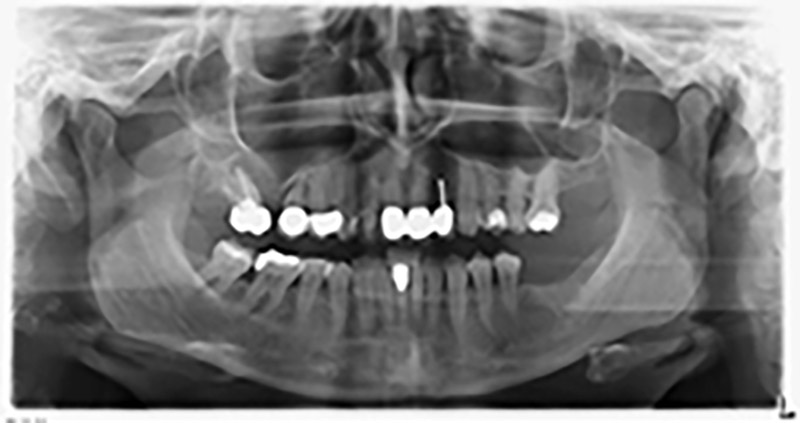

Ortopantomografia

Immagine 20: Ortopantomografia dopo il trattamento

Gli impianti applicati sono offerti da bredent e sono di tipo SKY (dente 16: 5,5 x 10 mm; dente 14: 4,0 x 10 mm).